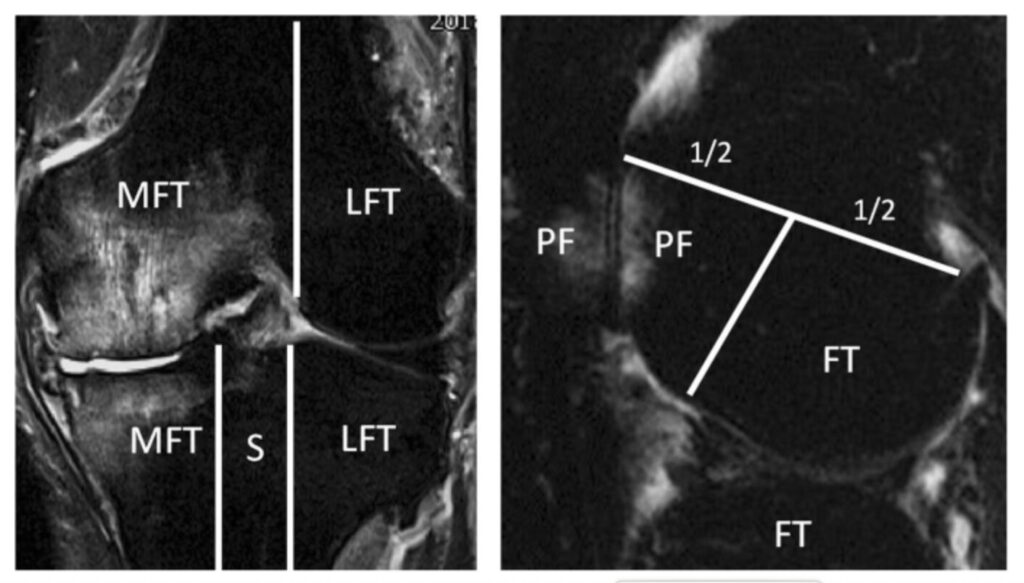

下の画像は膝のMRI画像でMFTの上下にある白くなっている部位が軟骨下骨髄病変とのこと。